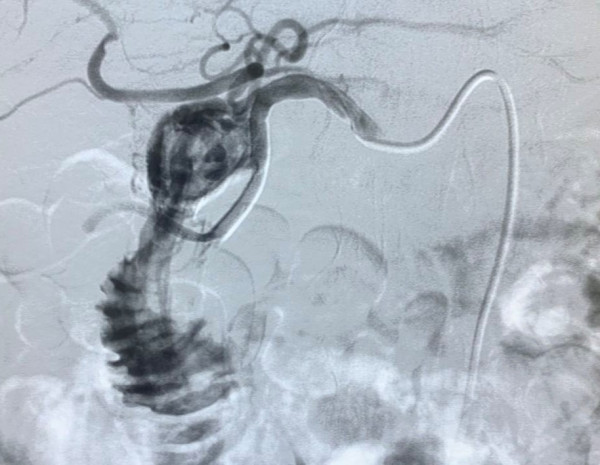

术中因患者失血过多、动脉搏动已几乎触摸不到,罗主任靠长期以来积累的手术经验迅速穿刺成功,并在最短的时间内完成血管造影并准确地找到出血责任血管。可见腹腔动脉一支分支血管有明细造影剂外溢,并可见肠道显影,遂超选择到责任血管并给予栓塞弹簧圈、明胶海绵颗粒、栓塞微球给予栓塞。

图1:术中造影发现十二指肠球部溃疡伴大出血